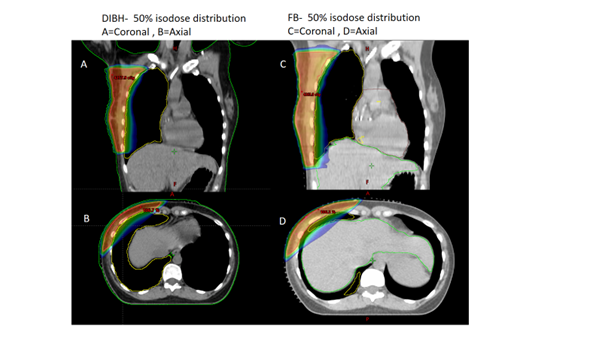

Quantifying benefit of deep inspiration breath hold technique in reducing cardiac avoidance area (CAA) and liver doses for right-sided breast cancer patients

Vikas Kumar Pandey, Anusheel Munshi, Asha Maria